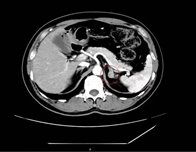

对于肾上腺腺瘤的诊断,需要综合运用多种检查手段。实验室检查如激素水平测定,有助于判断肿瘤是否具有功能性以及分泌的激素类型。影像学检查,如CT、MRI等,能够清晰地显示肿瘤的位置、大小、形态等特征,为诊断和治疗提供重要根据。

如果体检发现肾上腺腺瘤,首先要明确它是否“有功能”:通过CT或MRI明确腺瘤的大小、位置、形态,帮助判断性质。

肾上腺腺瘤CT表现

1.肾上腺腺瘤发生于肾上腺皮质,含脂质;

2.直径多小于3cm;

3.CT值<10HU;

4.出血、坏死、囊变少见;5.CT增强:早期快速廓清